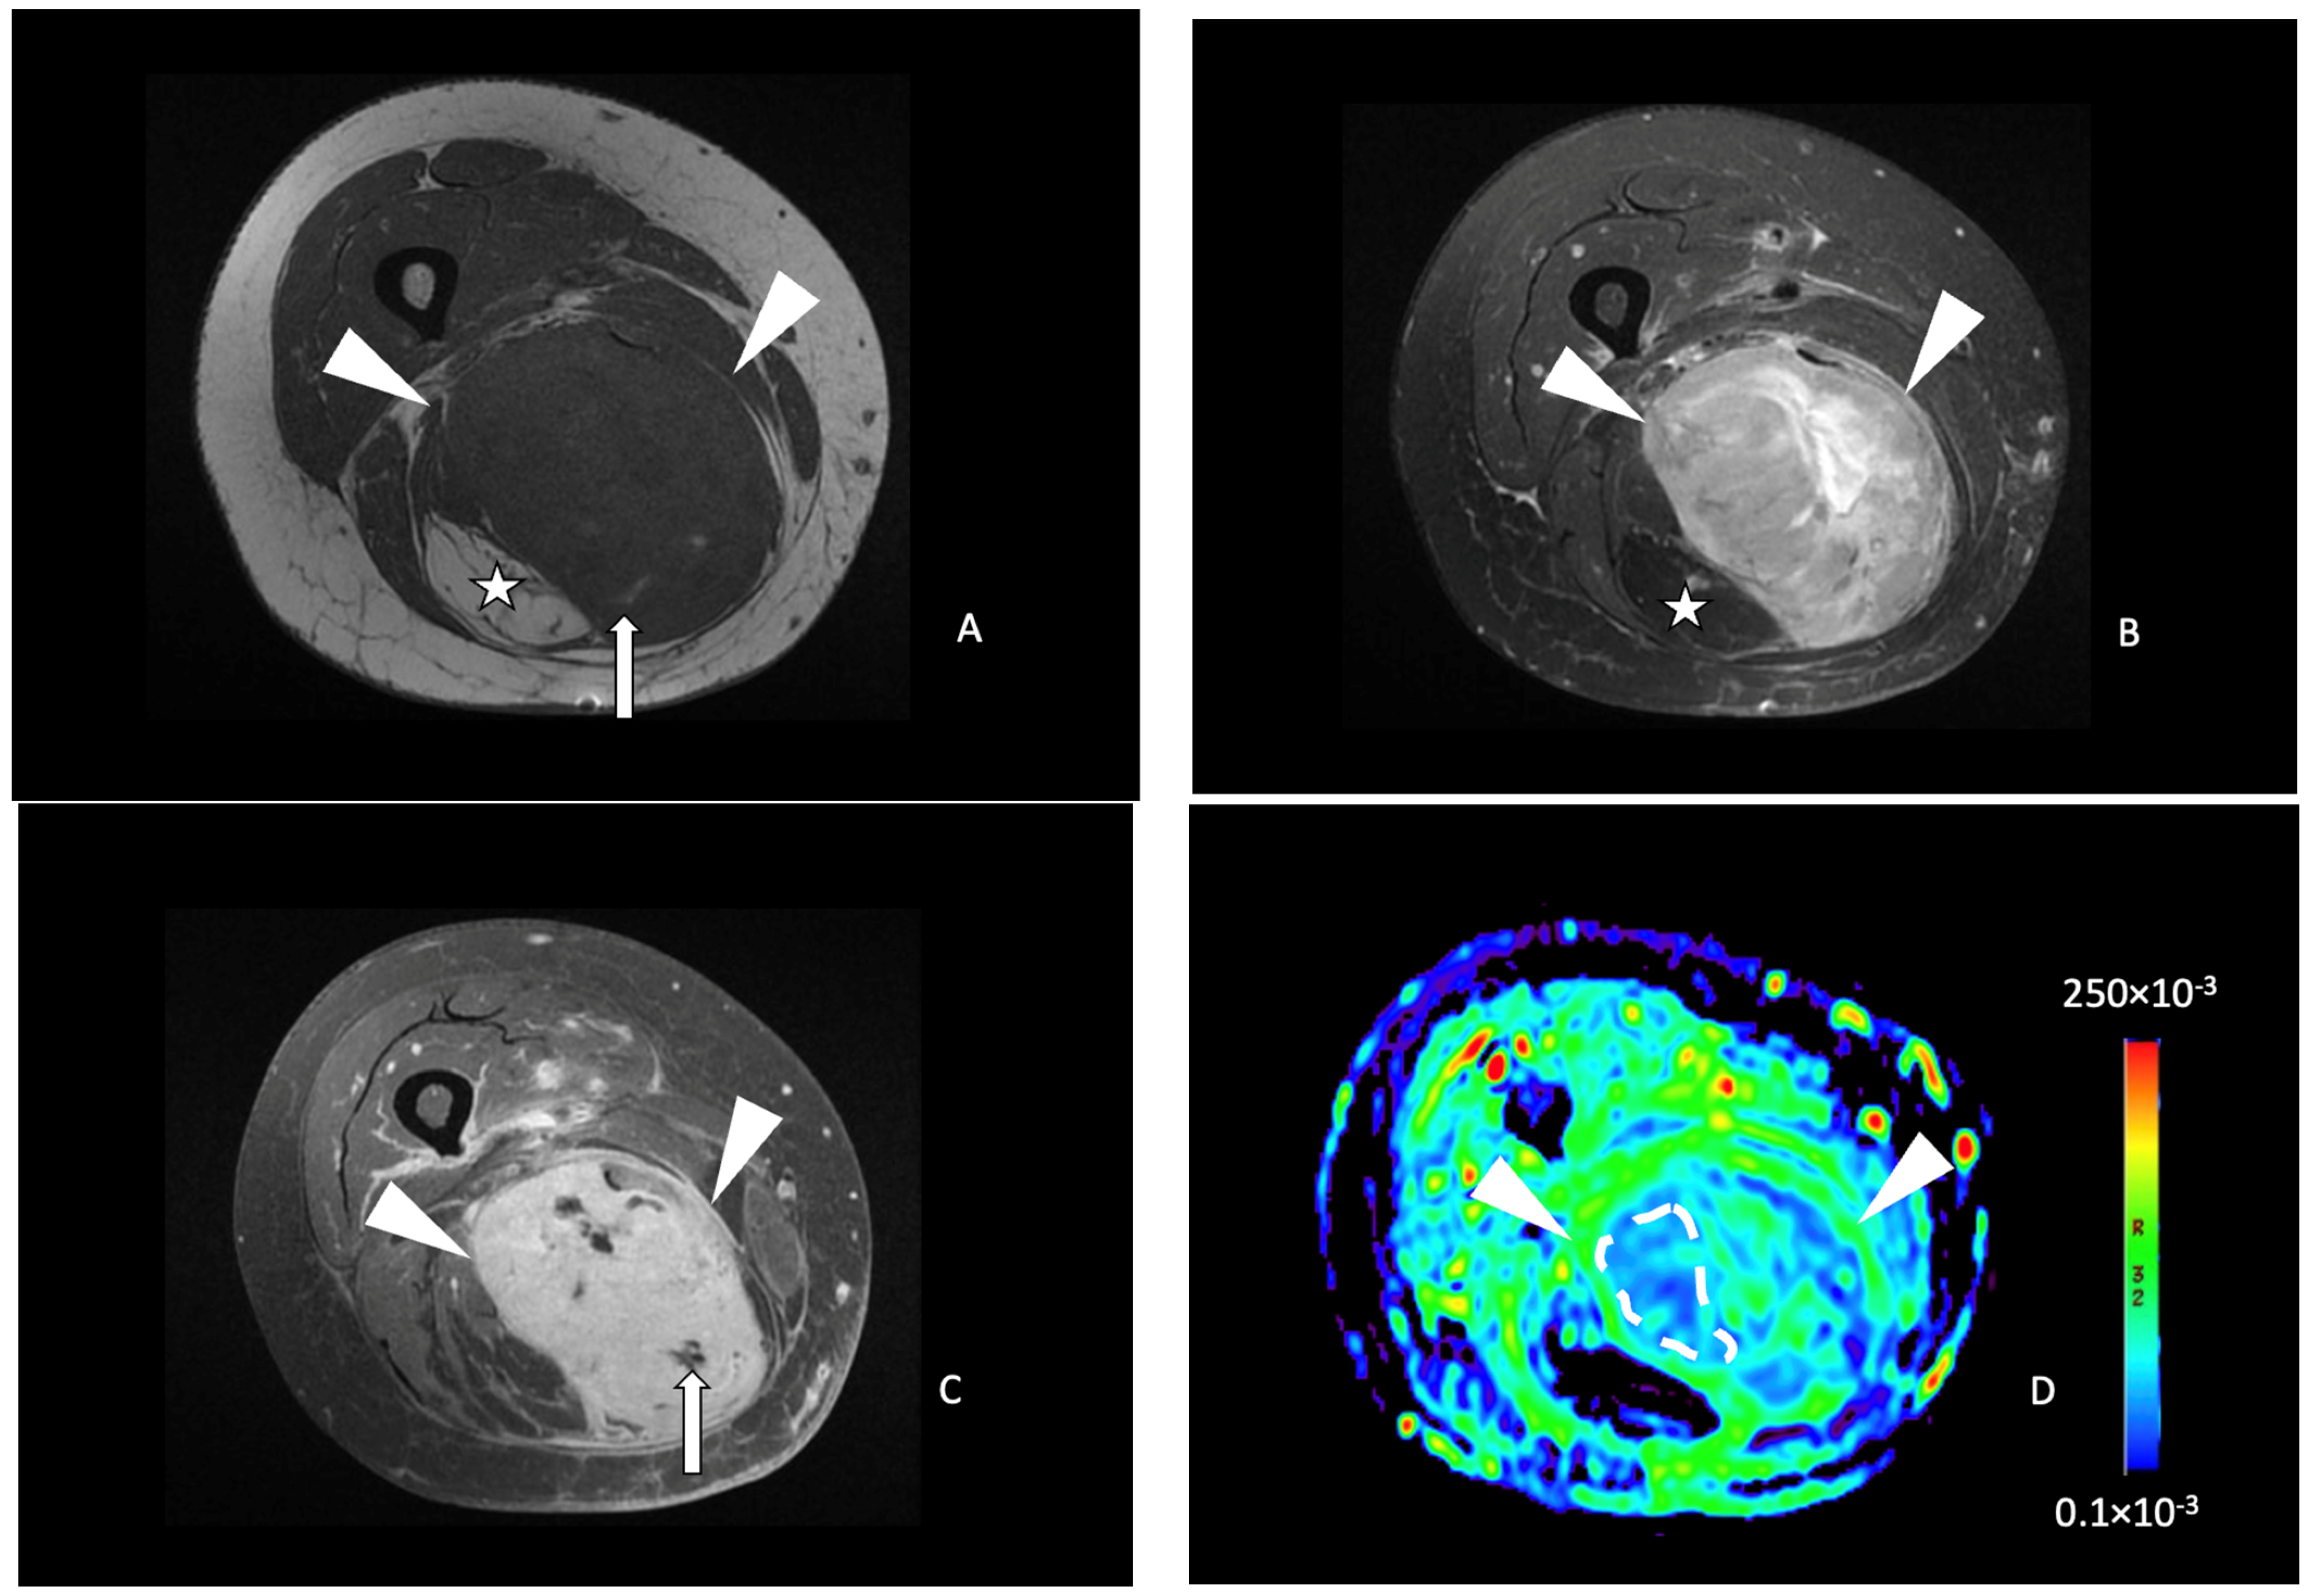

On ADC functional maps, the reader placed a free-form elliptical region of interest (ROI) on the solid tumor area that presented the lowest ADC value, based on the study of Bonarelli et al. [27]. The mean ADC value of the pixels in this ROI was considered to represent the minimal ADC of the tumor. The mean ADC value of skeletal muscle was obtained by placing another free-form elliptical ROI on normal-appearing muscle adjacent to the tumors evaluated of similar size (Figure 1). The tumor ADC ratio was calculated by dividing minimal tumor ADC by muscle ADC values.

Figure 1.

Functional imaging post-processing and analysis in a 69-year-old male with a leiomyosarcoma of the left popliteal fossa. Sagittal T2-weighted fat-saturated (A) and axial T1-weighted contrast-enhanced (B) MR images showing an ovoid mass (white arrowheads) with a heterogeneous hyperintense T2 signal and enhancement of the posterior compartment of the thigh in the popliteal fossa. (C) DCE (dynamic contrast-enhanced) AUC (area-under-the-curve) functional map in the axial plane showing a homogeneously enhancing tumor (arrowheads). Two free-form ROIs were placed. One on the area of highest tumor enhancement (green line) and another of the corresponding size in the muscle (white line). (D) Axial ADC (Apparent Diffusion Coefficient) functional map showing the same tumor (arrowheads). (E) An axial ADC functional map with an ROI of the corresponding size was drawn in the muscle (black line).

DCE AUC functional maps were evaluated, and the reader placed a free-form elliptical ROI on the tumor area most intensively enhancing and on a nearby artery. A second ROI of the corresponding size was placed on adjacent normal-appearing striated muscle. Tumor-to-muscle ratios were obtained by dividing tumor AUC by muscle AUC values.